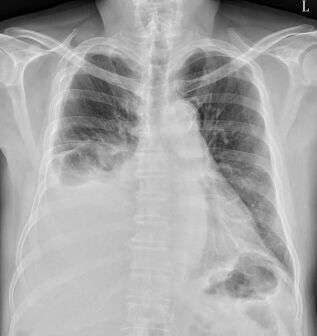

21. 黃先生68歲,有慢性阻塞性肺病(chronic obstructive pulmonary disease, COPD)的病史。因為發燒三天,合併呼吸急促與咳嗽有黃濃痰的狀況來到急診。黃先生自訴三個月前曾經因為慢性阻塞性肺病急性發 作(COPD exacerbation)住院一週,使用過類固醇與注射型抗生素。於急診時理學檢查發現呼吸急促,意識清楚。體溫 38.6°C, 心跳110 /minute, 血壓 136/80 mm Hg, 呼吸速率 26 /minute, 不使用氧氣的情況下SPO2: 91%,CXR如圖所示。WBC: 12,000 /mm³, platelet count: 159,000 per /mm³, BUN 26 mg /dl, creatinine 1.2 mg/dl。於急診的處置下列何者不適當?